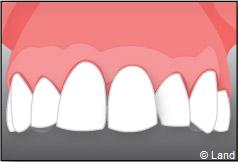

– le remplacement d’une dent unitaire. Grâce à ce procédé, il n’y a pas de mutilation des dents voisines.

Pour finir, une prothèse sera mise sur cet implant qui se comportera comme une racine artificielle.